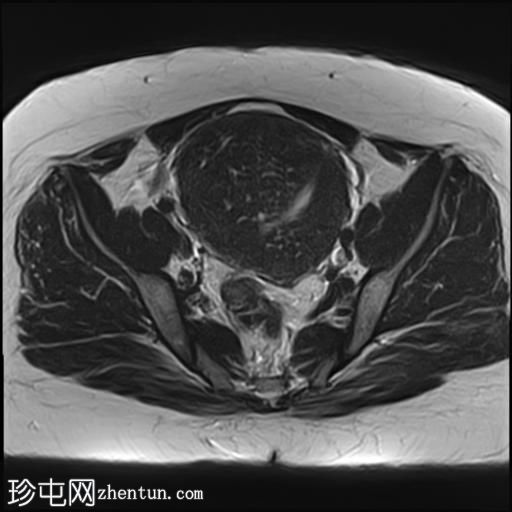

轴位

T1加权像

子宫增大,子宫内膜-肌层交界区弥漫性增厚,T1加权像呈中等信号,最高达45 mm;T2加权像呈低信号,内含多个小的高T2信号灶,提示月经出血渗入异位子宫内膜组织,符合弥漫性子宫腺肌症的

影像

学表现。

卵巢可见多个小的单房囊肿,无分隔或实性成分,最可能是浆液性包涵囊肿。

MRI表现最符合弥漫性子宫腺肌症。